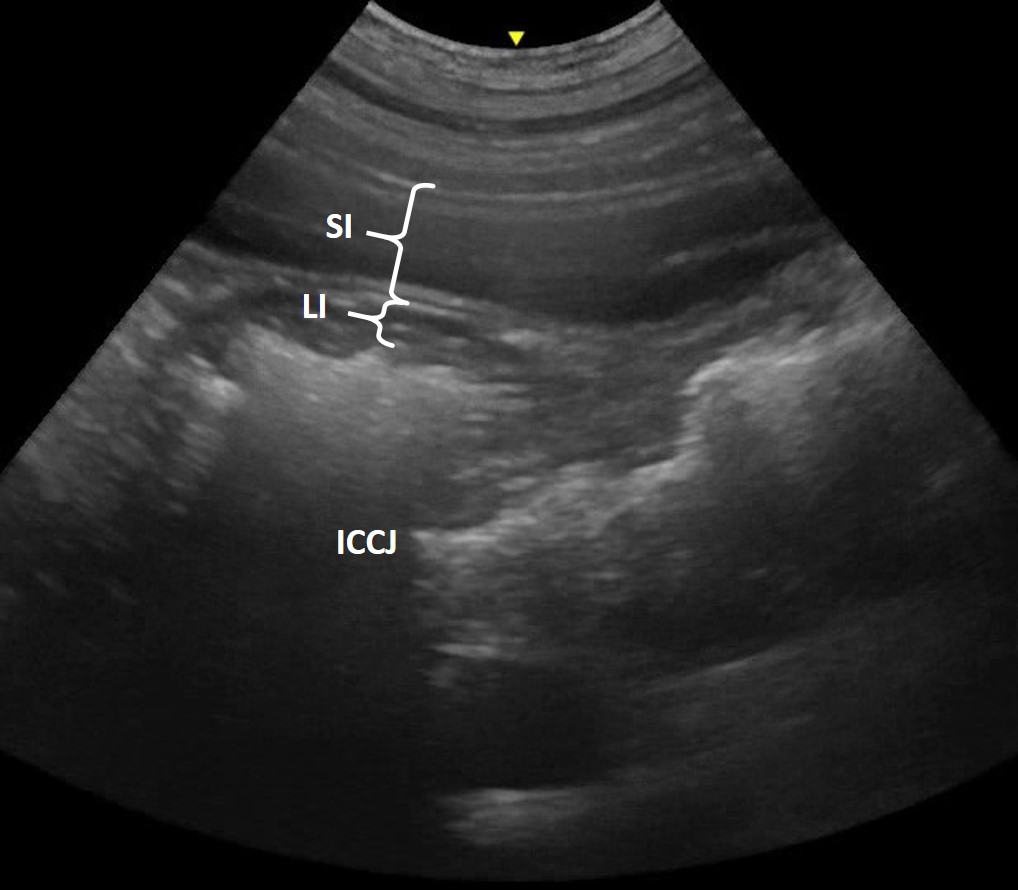

Colon

In comparison to the more proximal sections of GI tract, the colon has a much thinner total wall thickness, with layering which is more difficult to evaluate without a high frequency probe (Figure 7). Intraluminal gas and faecal contents commonly cause a distal acoustic shadowing artefact, which obscures the far wall.

Figure 7. Large Intestinal Wall Thickness – In this sagittal plane image of the right abdomen of a dog the ileo-caeco-colic junction (ICCJ) can be seen. The duodenum is visible in the near field (SI); note the marked difference in overall wall thickness between the small (SI; both walls highlighted) and large (LI; one wall highlighted) intestine.